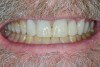

Fig 1. Pre-operative condition.

Figure 1

The patient was a 63-year-old male seeking a second opinion regarding restoring his mouth. He originally sought an opinion regarding extractions of his maxillary teeth and an all-on-four prosthesis. Upon examination, the patient had severe erosion of his teeth, especially the upper anteriors. Some teeth only had 1 mm to 3 mm of visible tooth structure. The lingual side had the most erosion. Additionally, there was some compensatory supra-eruption of the lower anterior teeth. The lower posterior teeth had occlusal and facial erosion. The upper posterior teeth were fracturing and wearing down. There was no anterior guidance. There was 3 mm to 4 mm probing of his periodontium and good bone support for his teeth.